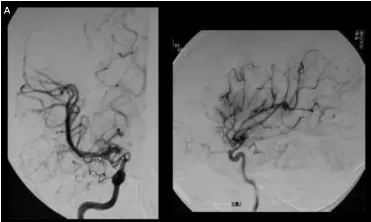

A:小春术前右颈血管造影显示,颈内动脉末端顶部血管烟雾弥漫性发育,大脑中动脉扩张。

相比之下,小春因早期发现和诊断,成功避免严重神经功能损伤。川岛教授为她实施颞浅动脉-大脑中动脉STA-MCA双吻合术后,未出现任何神经功能损伤,术后影像显示血供重建良好。